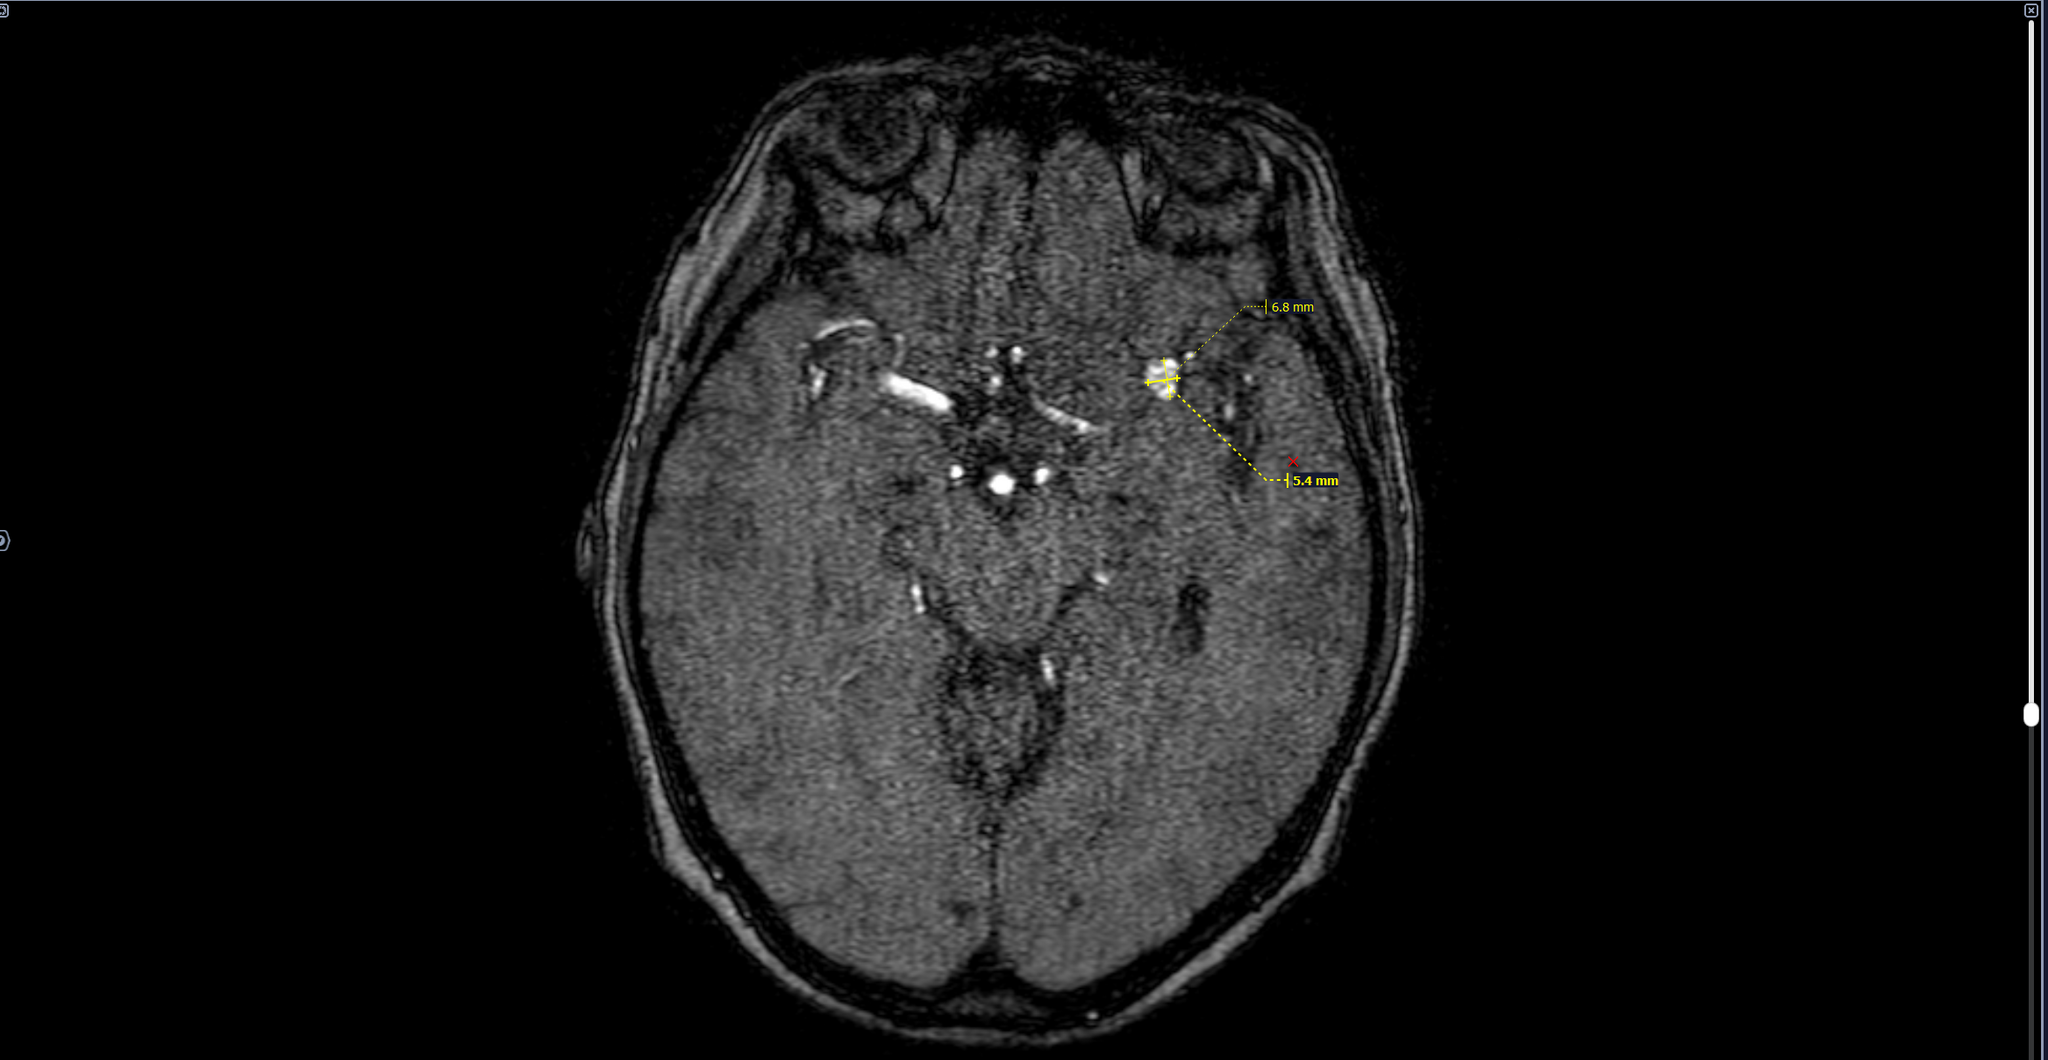

МР-картина мешотчатой аневризмы левой средней мозговой артерии на границе М1\М2 сегментов в области бифуркации размерами до 8.4х5.1 мм.